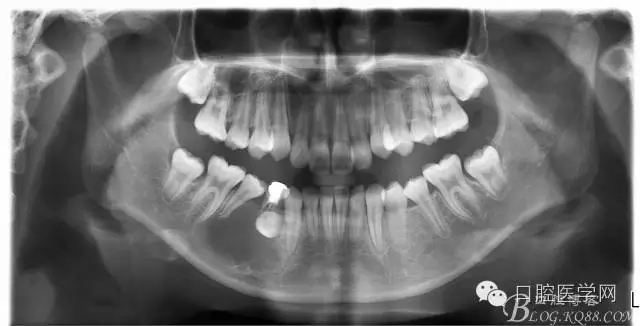

查:右側(cè)第二前磨牙第一乳磨牙恒尖牙頰側(cè)前庭溝隆起,捫有乒乓球感。曲斷及CT示:右側(cè)第二前磨牙第一乳磨牙恒尖牙根尖區(qū)有一囊腫,頰舌側(cè)骨板極薄,牙根無吸收,第二前磨牙牙根位于囊腫中,第一雙尖牙牙冠遠(yuǎn)中水平向阻生,牙冠位于囊腫中。經(jīng)協(xié)議:手術(shù)摘除創(chuàng)傷大,同意開創(chuàng)引流保守治療。

術(shù)后一個月 三個月 五個月 八個月 拔除第一雙尖牙后 曲斷片:

正畸查:替牙合。第一恒磨牙中性合。上牙弓尖圓型下牙弓方圓型。前牙覆合3度覆蓋7.5mm。下前牙咬到上舌側(cè)牙齦。上頜擁擠4.0mm,下頜擁擠

3.0mm。上頜稍前突下頜后縮,上下唇前突,上前牙覆蓋下唇,下唇外翻。面下三分之一過短,頦唇溝明顯,開唇露齒,頦饜窩明顯。顳下頜關(guān)節(jié)開閉口無彈響,無壓痛,開口型開口度正常。